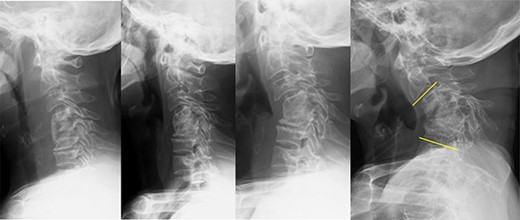

We planned a three-stage, anterior–posterior–anterior approach. In the first stage, we opted for a right-sided approach to reach the right VA. The VA was identified at the C3 level by resection of the C3 anterior tubercle of the transverse process. The VA was explored distally to the C4 vertebral body followed by resection of the C4 anterior wall. A piece of cotton was then inserted along the inner wall of the foramen transversum, the osteophyte was removed and the VA was separated from the vertebral body (Fig. 3). We performed subtotal corpectomy of C4–6 and total uncinectomy of C3/4 and C6/7; osteotomy proceeded without injuring the VA.

VA identification under the C3 anterior tubercle, and VA separation at the C4 vertebral body; (A) the abnormal VA in the C4 vertebra could not be directly confirmed even via the anterior cervical approach; VA was directly identified under the C3 anterior tubercle and then explored distally to secure the VA inside the C4 vertebral body; (B) after inserting a piece of cotton along the inner wall of the foramen transversum and removing the osteophyte, the VA could be separated from the C4 vertebral body.